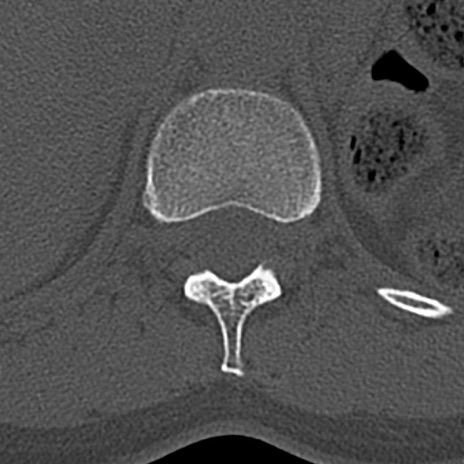

腰椎CT

横断像と矢状断像